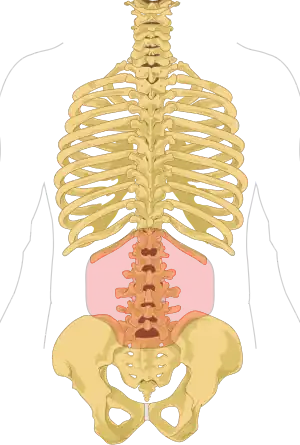

Regiunea lombară constă în cinci vertebre (L1-L5). Între acestea se află discuri fibrocartilaginoase, care acționează ca niște perne, împiedicând frecarea intervertebrală și protejând măduva spinării. Nervii vin de la și se îndreaptă către măduva spinării prin intermediul canalelor specifice dintre vertebre, dând pielii simțul tactil și trimițând mesaje mușchilor. Stabilitatea coloanei este dată de ligamentele și mușchii spatelui și abdomenului. Articulațiile mici, denumite articulații fațetare, limitează și controlează mișcarea coloanei.[12]